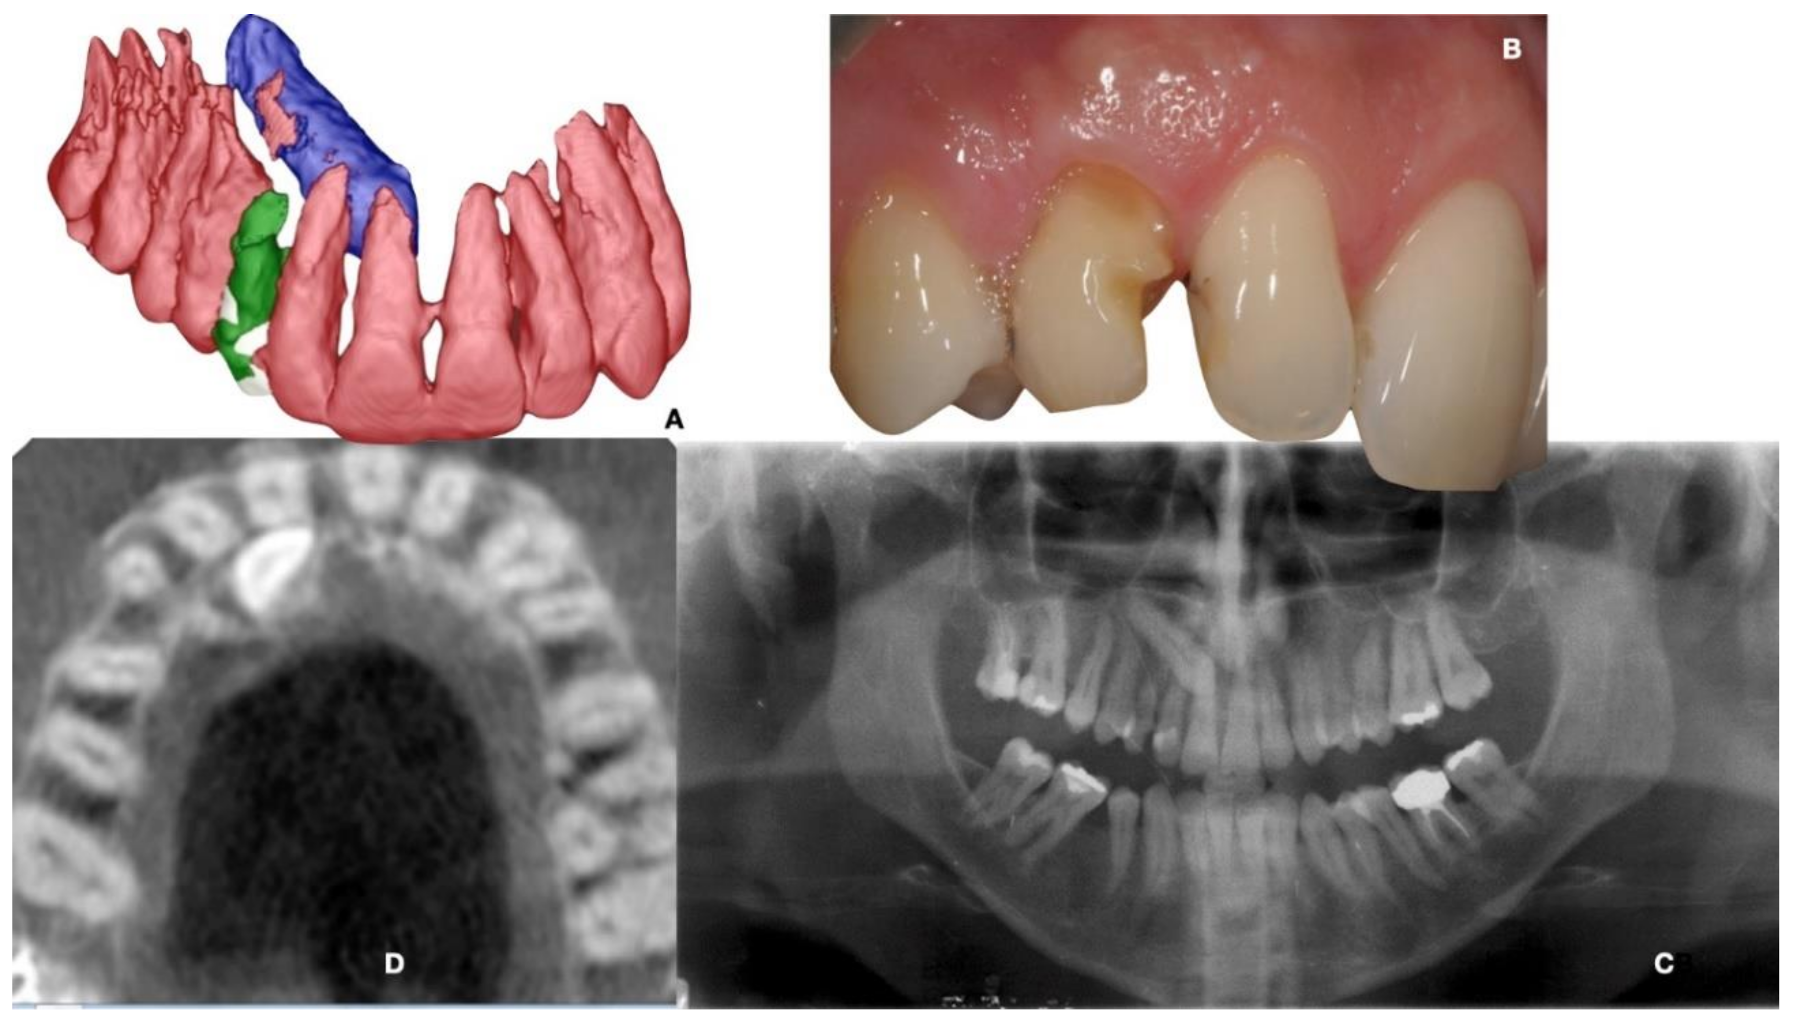

| (a) Surgical removal of the deciduous tooth and orthodontic extrusion, and taking in occlusion of the permanent canine |

| (b) Conservative treatment of the deciduous tooth living in situ with the impacted canine |

| (c) Removal of the deciduous tooth and involvement of the adjacent natural elements for a fixed conventional or adhesive bridge living in situ with the impacted canine |

| (d) Removal of the deciduous tooth and replacement with implant-borne-prosthesis living in situ with the impacted canine, accepting the compromise of involving the impacted tooth in the implant seating procedure |

| (e) Surgical removal of the impacted canine and, in a second stage, removal of the deciduous tooth and replacement with implant-borne-prosthesis |